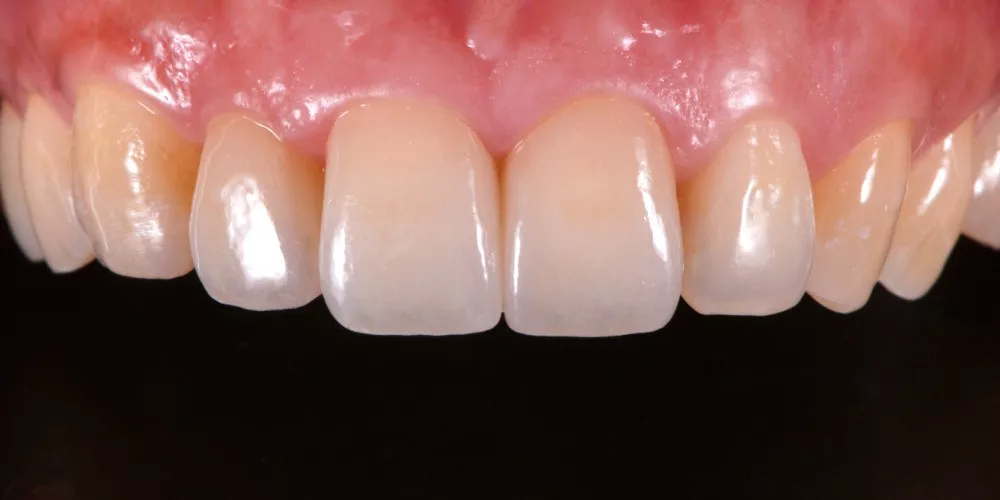

因此,每一次的治療,我都傾注最大的心力,在品質及細節上堅守高標準,讓成果真正經得起考驗。

一副笑容的改變,帶來的不只是外觀的提升,更深刻影響一個人在職場、人際與生活中的自信。相反的,一顆做得不夠好、撐不久的牙齒,或許短期內無痛無礙,卻會在無形中逐漸消磨一個人對生活的底氣。